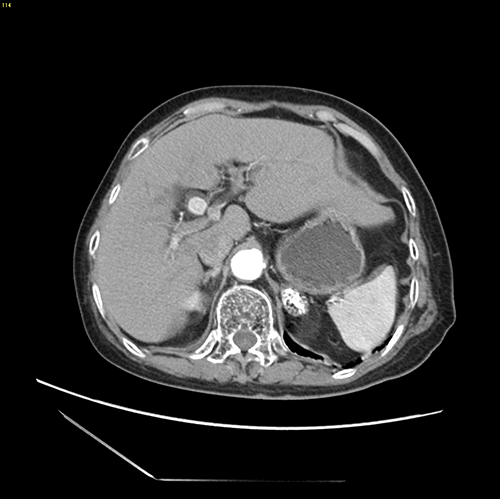

肝内外胆管结石-腹腔镜左半肝切除、 胆囊切除、胆总管切开取石、T管引流